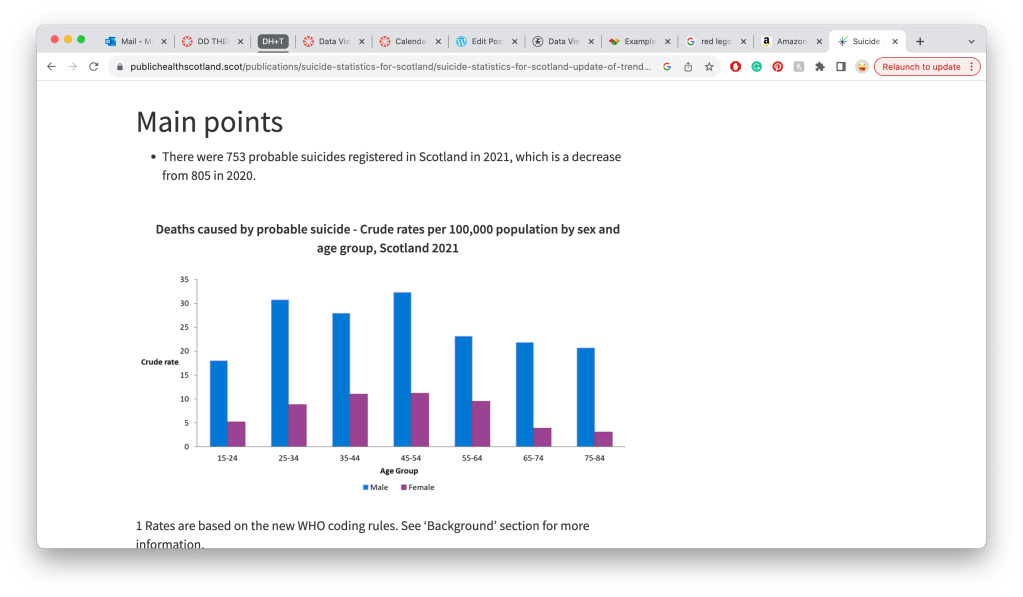

Mens mental health:

https://www.gov.scot/publications/scottish-health-survey-2021-volume-1-main-report/pages/7/